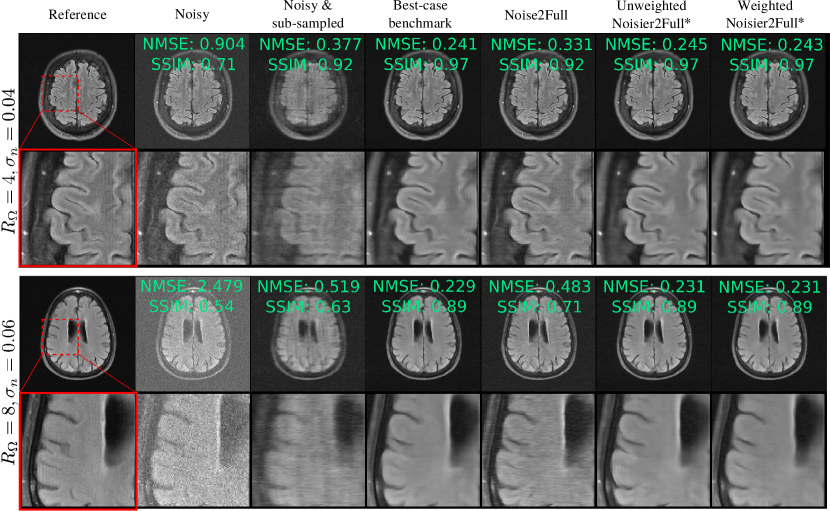

Figure 5: Reconstructions when fully sampled, noisy data is available for training. “Noisy” and “Noisy & sub-sampled” refer to the RSS reconstruction of y0,s+nssubscript𝑦0𝑠subscript𝑛𝑠y_{0,s}+n_{s} and MΩs(y0,s+ns)subscript𝑀subscriptΩ𝑠subscript𝑦0𝑠subscript𝑛𝑠M_{\Omega_{s}}(y_{0,s}+n_{s}) respectively. While there is clear noise in Noise2Full’s reconstruction, the proposed methods, which are indicated with an asterisk, perform very similarly to the best-case benchmark.

V-C Task A: Fully sampled, noisy training data

Fig. 6 shows the how the test set loss of networks trained on fully sampled, noisy data compares with the best-case benchmark. Noise2Full’s performance significantly degrades as σnsubscript𝜎𝑛\sigma_{n} increases: for RΩ=8subscript𝑅Ω8R_{\Omega}=8 and σn=0.08subscript𝜎𝑛0.08\sigma_{n}=0.08, Noise2Full’s test set loss is approximately double that of the best-case benchmark. In contrast, Weighted Noisier2Full performs similarly to the benchmark: for all σnsubscript𝜎𝑛\sigma_{n} and RΩsubscript𝑅ΩR_{\Omega}, Weighted Noisier2Full was within 0.09dB of the best-case benchmark. The performance of unweighted Noisier2Full was slightly poorer than the weighted version, especially for high noise levels at the more challenging acceleration factor RΩ=8subscript𝑅Ω8R_{\Omega}=8. Two reconstruction examples are shown in Fig. 5. Here, and throughout this paper, the example reconstructions show the image domain RSS cropped to a central 320×320320320320\times 320 region. The k-space Normalized Mean-Squared Error (NMSE) and Structural Similarity (SSIM) [37] are also shown, where the SSIM is computed on the magnitude image with the background excluded via the mask from the ESPIRiT algorithm [38], which we implemented with the BART toolbox [39].

The pseudo-denoising effect described in Section III is visible in Fig. 5, which shows less noise in Noise2Full than Noisy. We note that the NMSE of Noisy is roughly 4 and 8 times larger than Noise2Full for RΩ=4,8subscript𝑅Ω48R_{\Omega}=4,8 respectively, consistent with the theoretical finding that Noise2Full does not remove the measurement noise in the input. A comparison of figures 6 and 8 shows that Standard SSDU performs very similarly to Noise2Full quantitatively, exhibiting a similar pseudo-denoising effect.